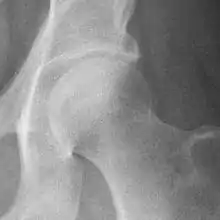

Osteoarthritis of the hip joint may also be graded by Tönnis classification. There is no consensus whether it is more or less reliable than the Kellgren-Lawrence system.[8]

| Grade | Description |

|---|---|

| 0 | No osteoarthritis signs |

| 1 | Mild:

|

| 2 | Moderate:

| 3 | Severe: